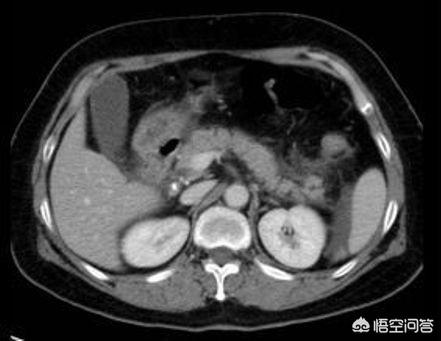

2.关于胰腺炎的诊断 其实临床慢性胰腺炎很少见 慢性胰腺炎非常痛苦 这里就不赘述了 主要说一说急性胰腺炎的诊断 临床大夫都知道淀粉酶 脂肪酶 其实这是严重错误的 绝不能单单依靠这个来诊断 胰腺炎真多需要:临床腹痛症状 影像学(腹部ct下胰腺周围渗出) 血淀粉酶(注意是血淀粉酶不是尿淀粉酶)三倍以上 这三个条件三个有两个符合方可诊断 单单依靠淀粉酶是非常不严谨有时候会耽误病情 因为淀粉酶升高下降是有时间波峰的 曾经收治过一个很重的胰腺炎患者 刚住院时查腹部ct 淀粉酶 血常规都正常 结果腹痛持续性加重 过了六小时复查 胰腺周围渗出 淀粉酶 血象全都上来了 另一方面说有时候淀粉酶升高也不一定就是胰腺炎 有的时候肠道梗阻 溃疡病 胆囊炎等也会升高 所以不能单单依靠淀粉酶来判断病情 要综合分析 还有尿淀粉酶这个就更没有很大的参考意义了 最新的教科书已经不提尿淀粉酶了 这里就不赘述了